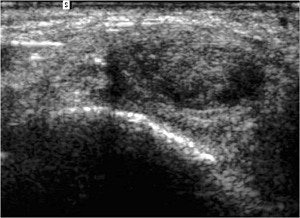

| In this case, ultrasound studies led to a diagnosis of PTT tendinosis with a partial tear (top and bottom), while T1-weighted MR image (center) indicated a complete tear. The patient was treated for a partial tear, however, as the orthopedic surgeon's evaluation of the PTT was more consistent with the ultrasound findings. Images courtesy of Dr. Krishna Nallamshetty. |

None of the discordant readings affected patient management because the clinical symptoms were more consistent with the ultrasound diagnosis, Nallamshetty said. Limitations of the study included a small sample size, an imperfect gold standard, and lack of surgical correlation, he said.